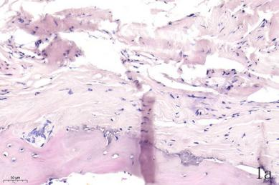

NDN(Necdin)属于黑色素瘤抗原(MAGE)家族,由60多个基因构成共享高度保守的MAGE同源结构域(MHD)[6,7]。最近几年的研究提出NDN是一种新的抑癌基因,其在卵巢癌[8]、乳腺癌[9]和黑色素瘤[10]等的组织和细胞系中低表达,过表达NDN可以抑制其生长,但NDN在骨肉瘤中的作用及机制尚不清楚。为探讨NDN在骨肉瘤中的作用及途径,我们收集了骨肉瘤患者的石蜡标本以及临床信息,对其进行了免疫组化检测及生存分析通过对骨组织和骨肉瘤HE染色发现,骨组织组,骨密质呈板层状,陷窝中可见骨细胞呈梭形排列( 图1 a 1b) ;骨肉瘤组,瘤细胞呈多角形,核大深染,核分裂多见,瘤细胞呈车辐状排列,瘤细胞间可见少量肿瘤性骨质形成(图1c1d)。同时通过免疫组化发现,NDN表达主要位于细胞的胞核中。NDN在骨肉瘤组织中的表达率为29.4%(15/51)(图1c1d),明显低于瘤旁骨组织阳性表达率80%(8/10)(图1a1b)。